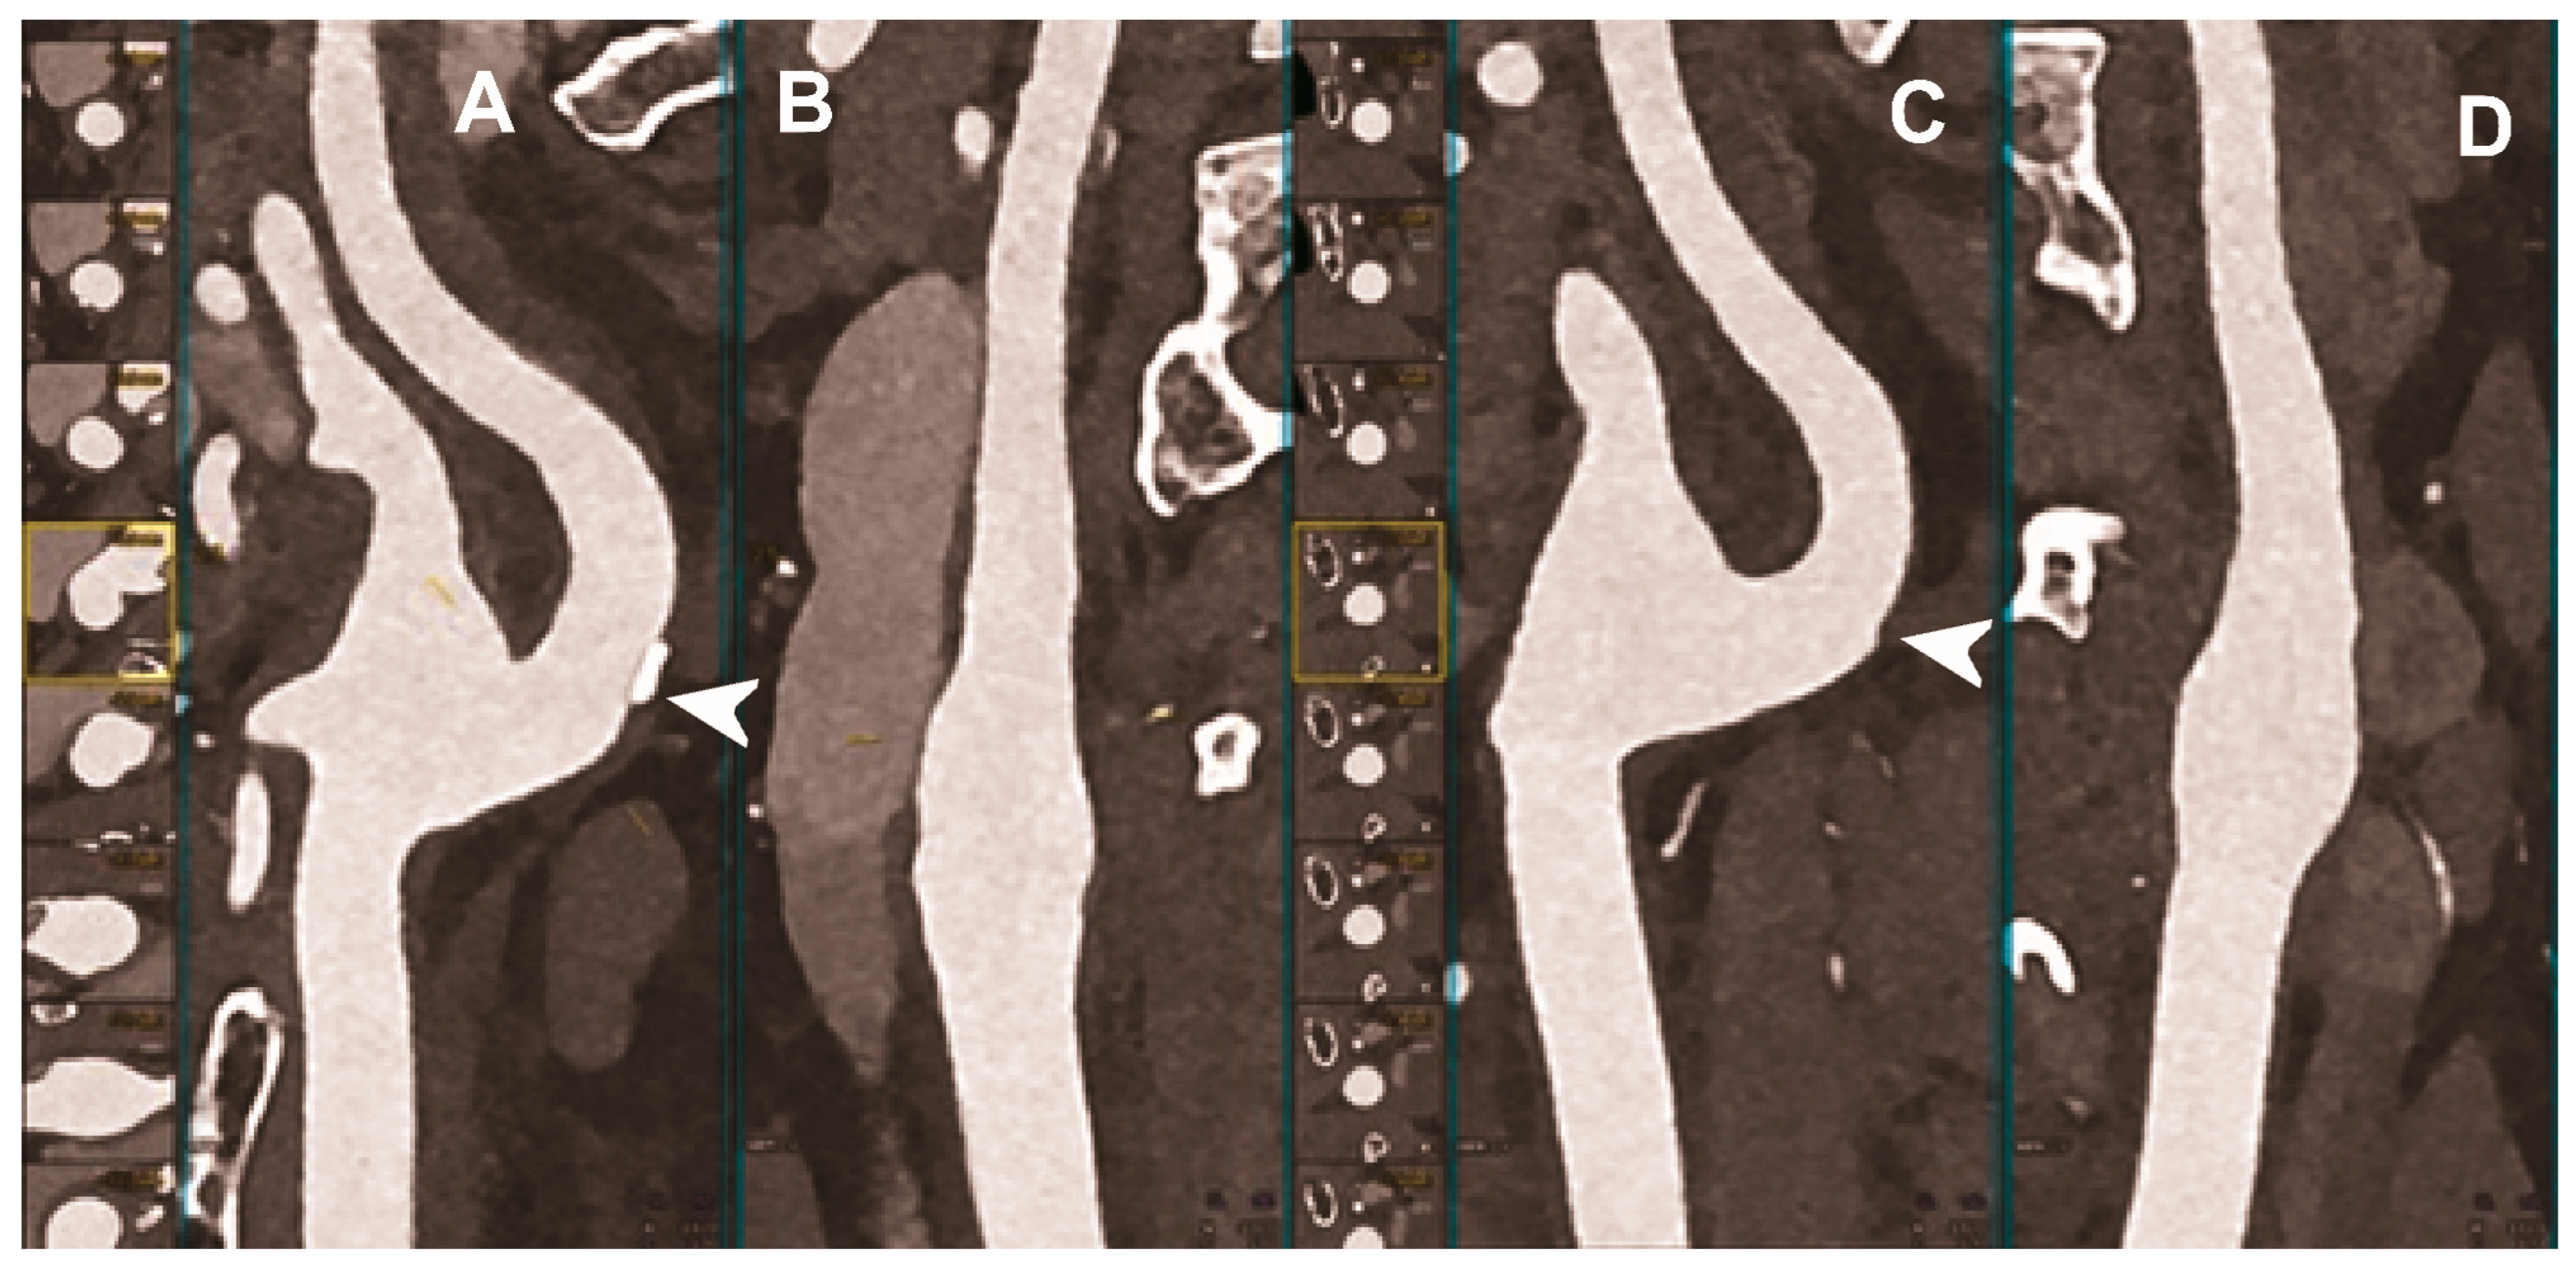

| Symons et al. 2018 [49] | Clinical (16 asymptomatic subjects). |

|

- Symons, R.; Reich, D.S.; Bagheri, M.; Cork, T.E.; Krauss, B.; Ulzheimer, S.; Kappler, S.; Bluemke, D.A.; Pourmorteza, A. Photon-Counting Computed Tomography for Vascular Imaging of the Head and Neck: First In Vivo Human Results. Invest. Radiol. 2018, 53, 135–142. [Google Scholar] [CrossRef]